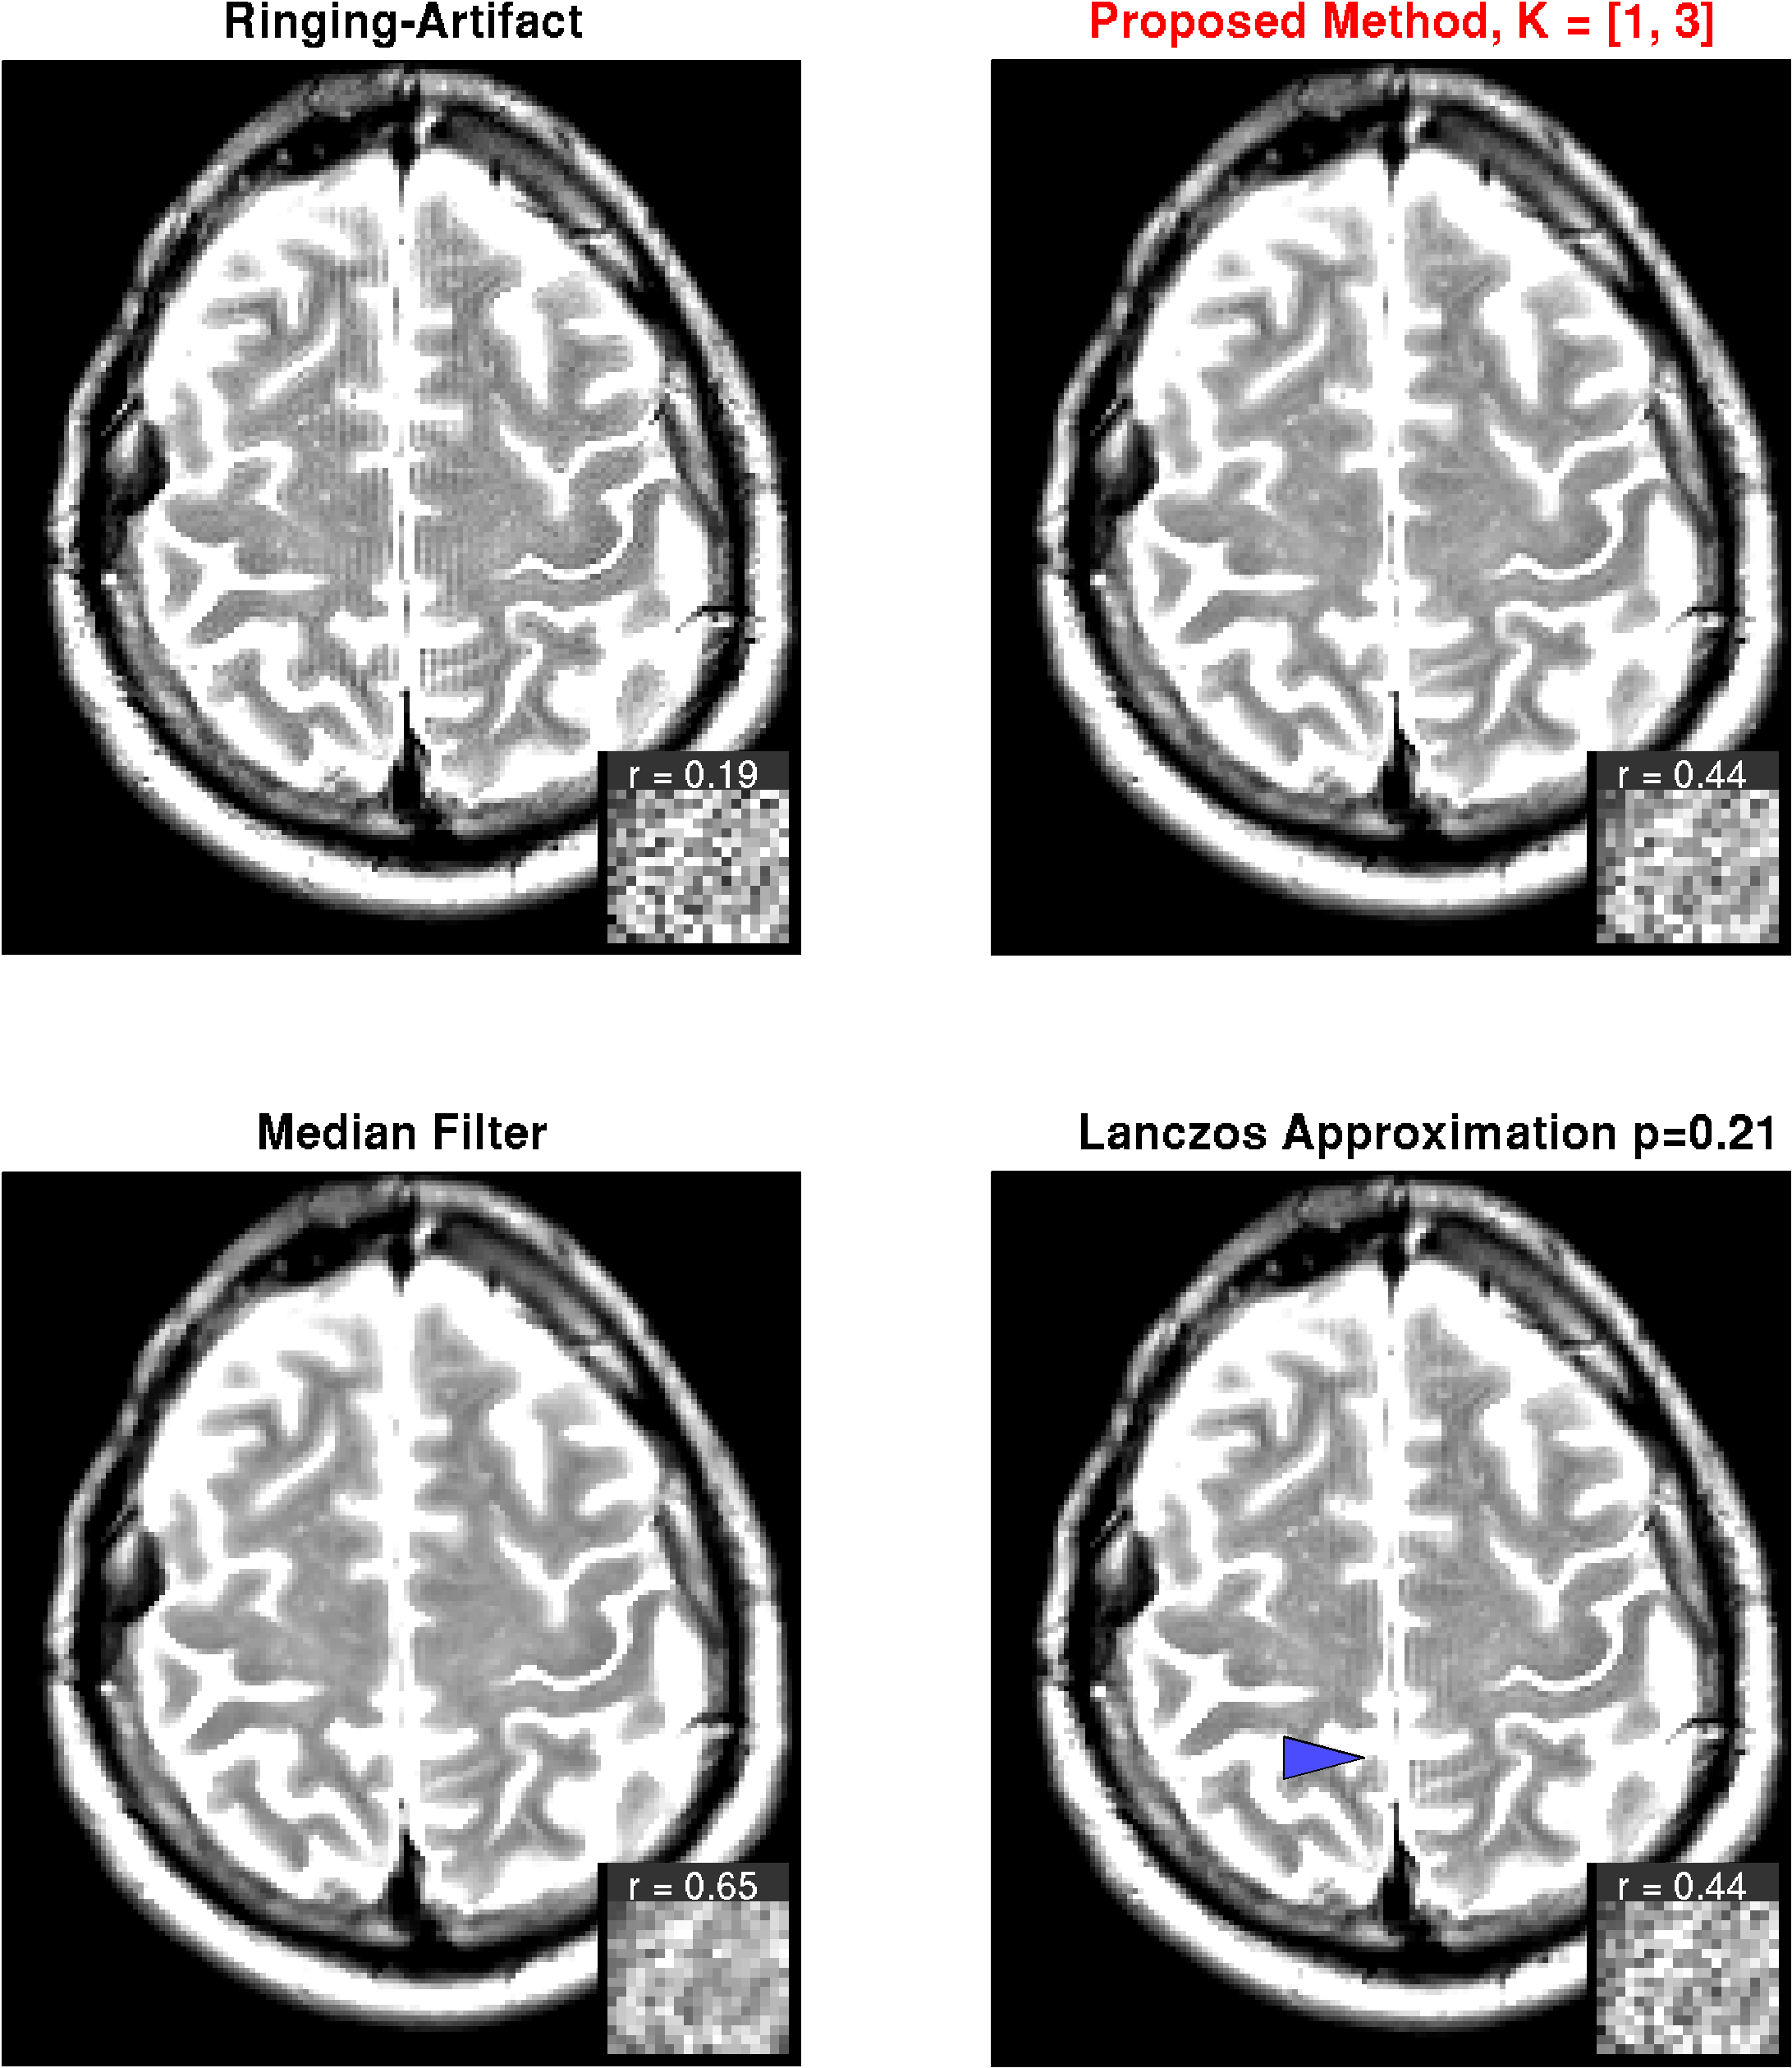

MRI images

The results for DWI measurements are shown for one slice in Fig. 6. Apparently, the -images exhibit strong ringing artifacts, which is even more emphasized after diffusion calculation. The artifact can be reduced with both, the median filter and the Lanczos approximation with , however, at the cost of strong smoothing. With the proposed method on the other hand, the artifact can virtually completely be removed with minimal filtering. Results from the -weighted image given in Fig. 7. The findings are basically the same as for the DWI measurement.